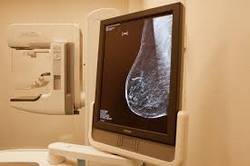

Для проведения исследования используются специальные аппараты – маммографы. Сама маммография не занимает много времени. Для получения хорошего снимка грудь фиксируется и слегка сжимается двумя планками. Необходимо выполнение двух снимков в разных проекциях для получения наиболее верного результата. Процесс абсолютно безболезненный.

Особенности: рентгеновский аппарат для проведения исследования «маммография» позволяет получить цифровой снимок.

Особенности: используется высокоточный маммограф производства Италии.

Особенности: используется уникальная цифровая маммография, которая дает возможность 3-мерного томосинтеза. Возможность проведения всех исследований молочной железы в одной клинике.